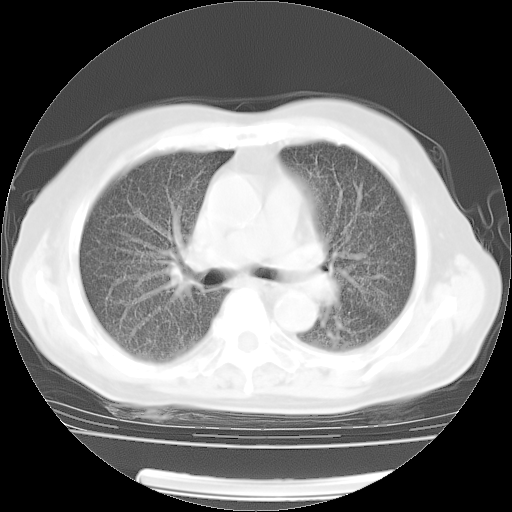

4月14日肺部CT

23.JPG

24.JPG

25.JPG

26.JPG